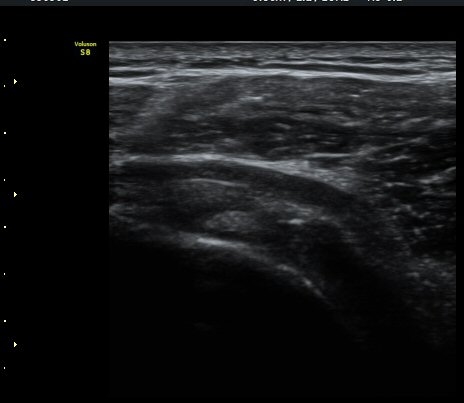

±Ø»ó°Ç ¸»´ÜºÎ Á¾´Ü¸é°Ë»ç¿¡¼­ ±Ø»ó°Ç°ú Á¡¾×³¶³» ¼®È¸È­°¡ °üÂûµÈ´Ù(±×¸² 4, 5).